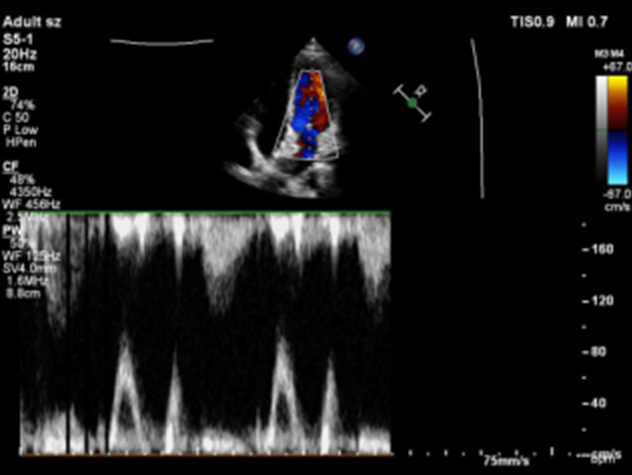

术后6个月随访

超声报告:(1)房间隔封堵器位置正常,伞盘可见部分降解,各瓣叶形态活动未见异常,右心比例稍大,左房室腔不大,心包腔内未见液性暗区; (2)多普勒检查:房水平未见残余分流;心功能:室壁运动协调,未见节段性异常;(3)先天性心脏病房间隔缺损封堵术后(可降解)未见残余分流。